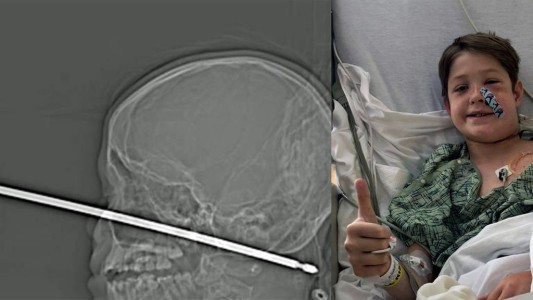

El milagro del nene que sobrevivió pese a clavarse una enorme aguja en la cabeza